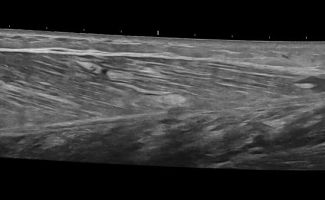

- Κατηγοριοποίηση (Grading) Θλάσεων Μυών: Το Υπερηχογράφημα Μυών μπορεί να αποτελέσει ιδανικό εργαλείο για την ανίχνευση και εκτίμηση της έκτασης μυϊκών θλάσεων μετά από τραυματισμό ή άλλα μυϊκά προβλήματα.

- Δυναμική Εξέταση: Με το Υπερηχογράφημα Μυών μπορούμε να παρατηρήσουμε τους μύες κατά τη διάρκεια διαφόρων κινήσεων, κάτι που μας επιτρέπει να ανιχνεύσουμε μυϊκές ανωμαλίες που ενδέχεται να μην είναι ορατές σε στατικές εικόνες.